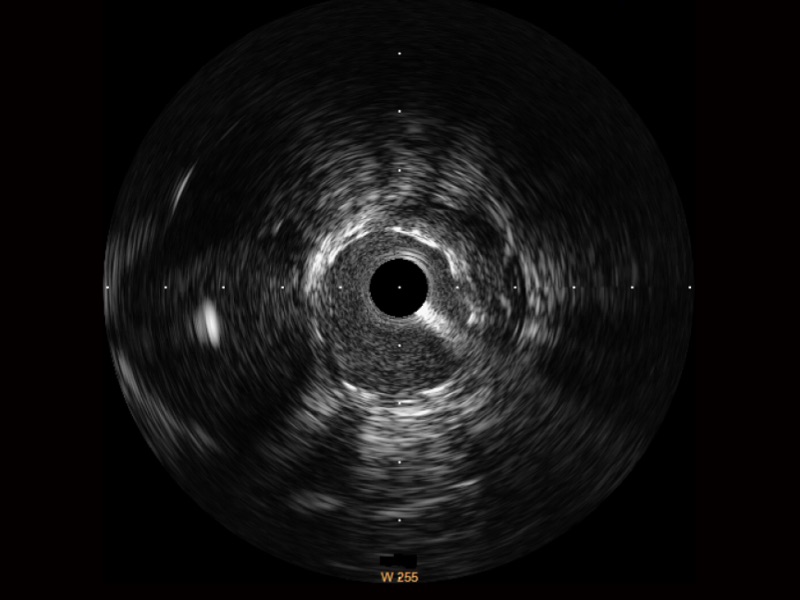

传统IVUS图像

对比传统IVUS导管成像,米兰官方网站宽频IVUS图像的近场支架梁显影更细腻,远场中膜外血管仍清晰可辨,兼顾远中近,兼顾分辨力与穿透深度